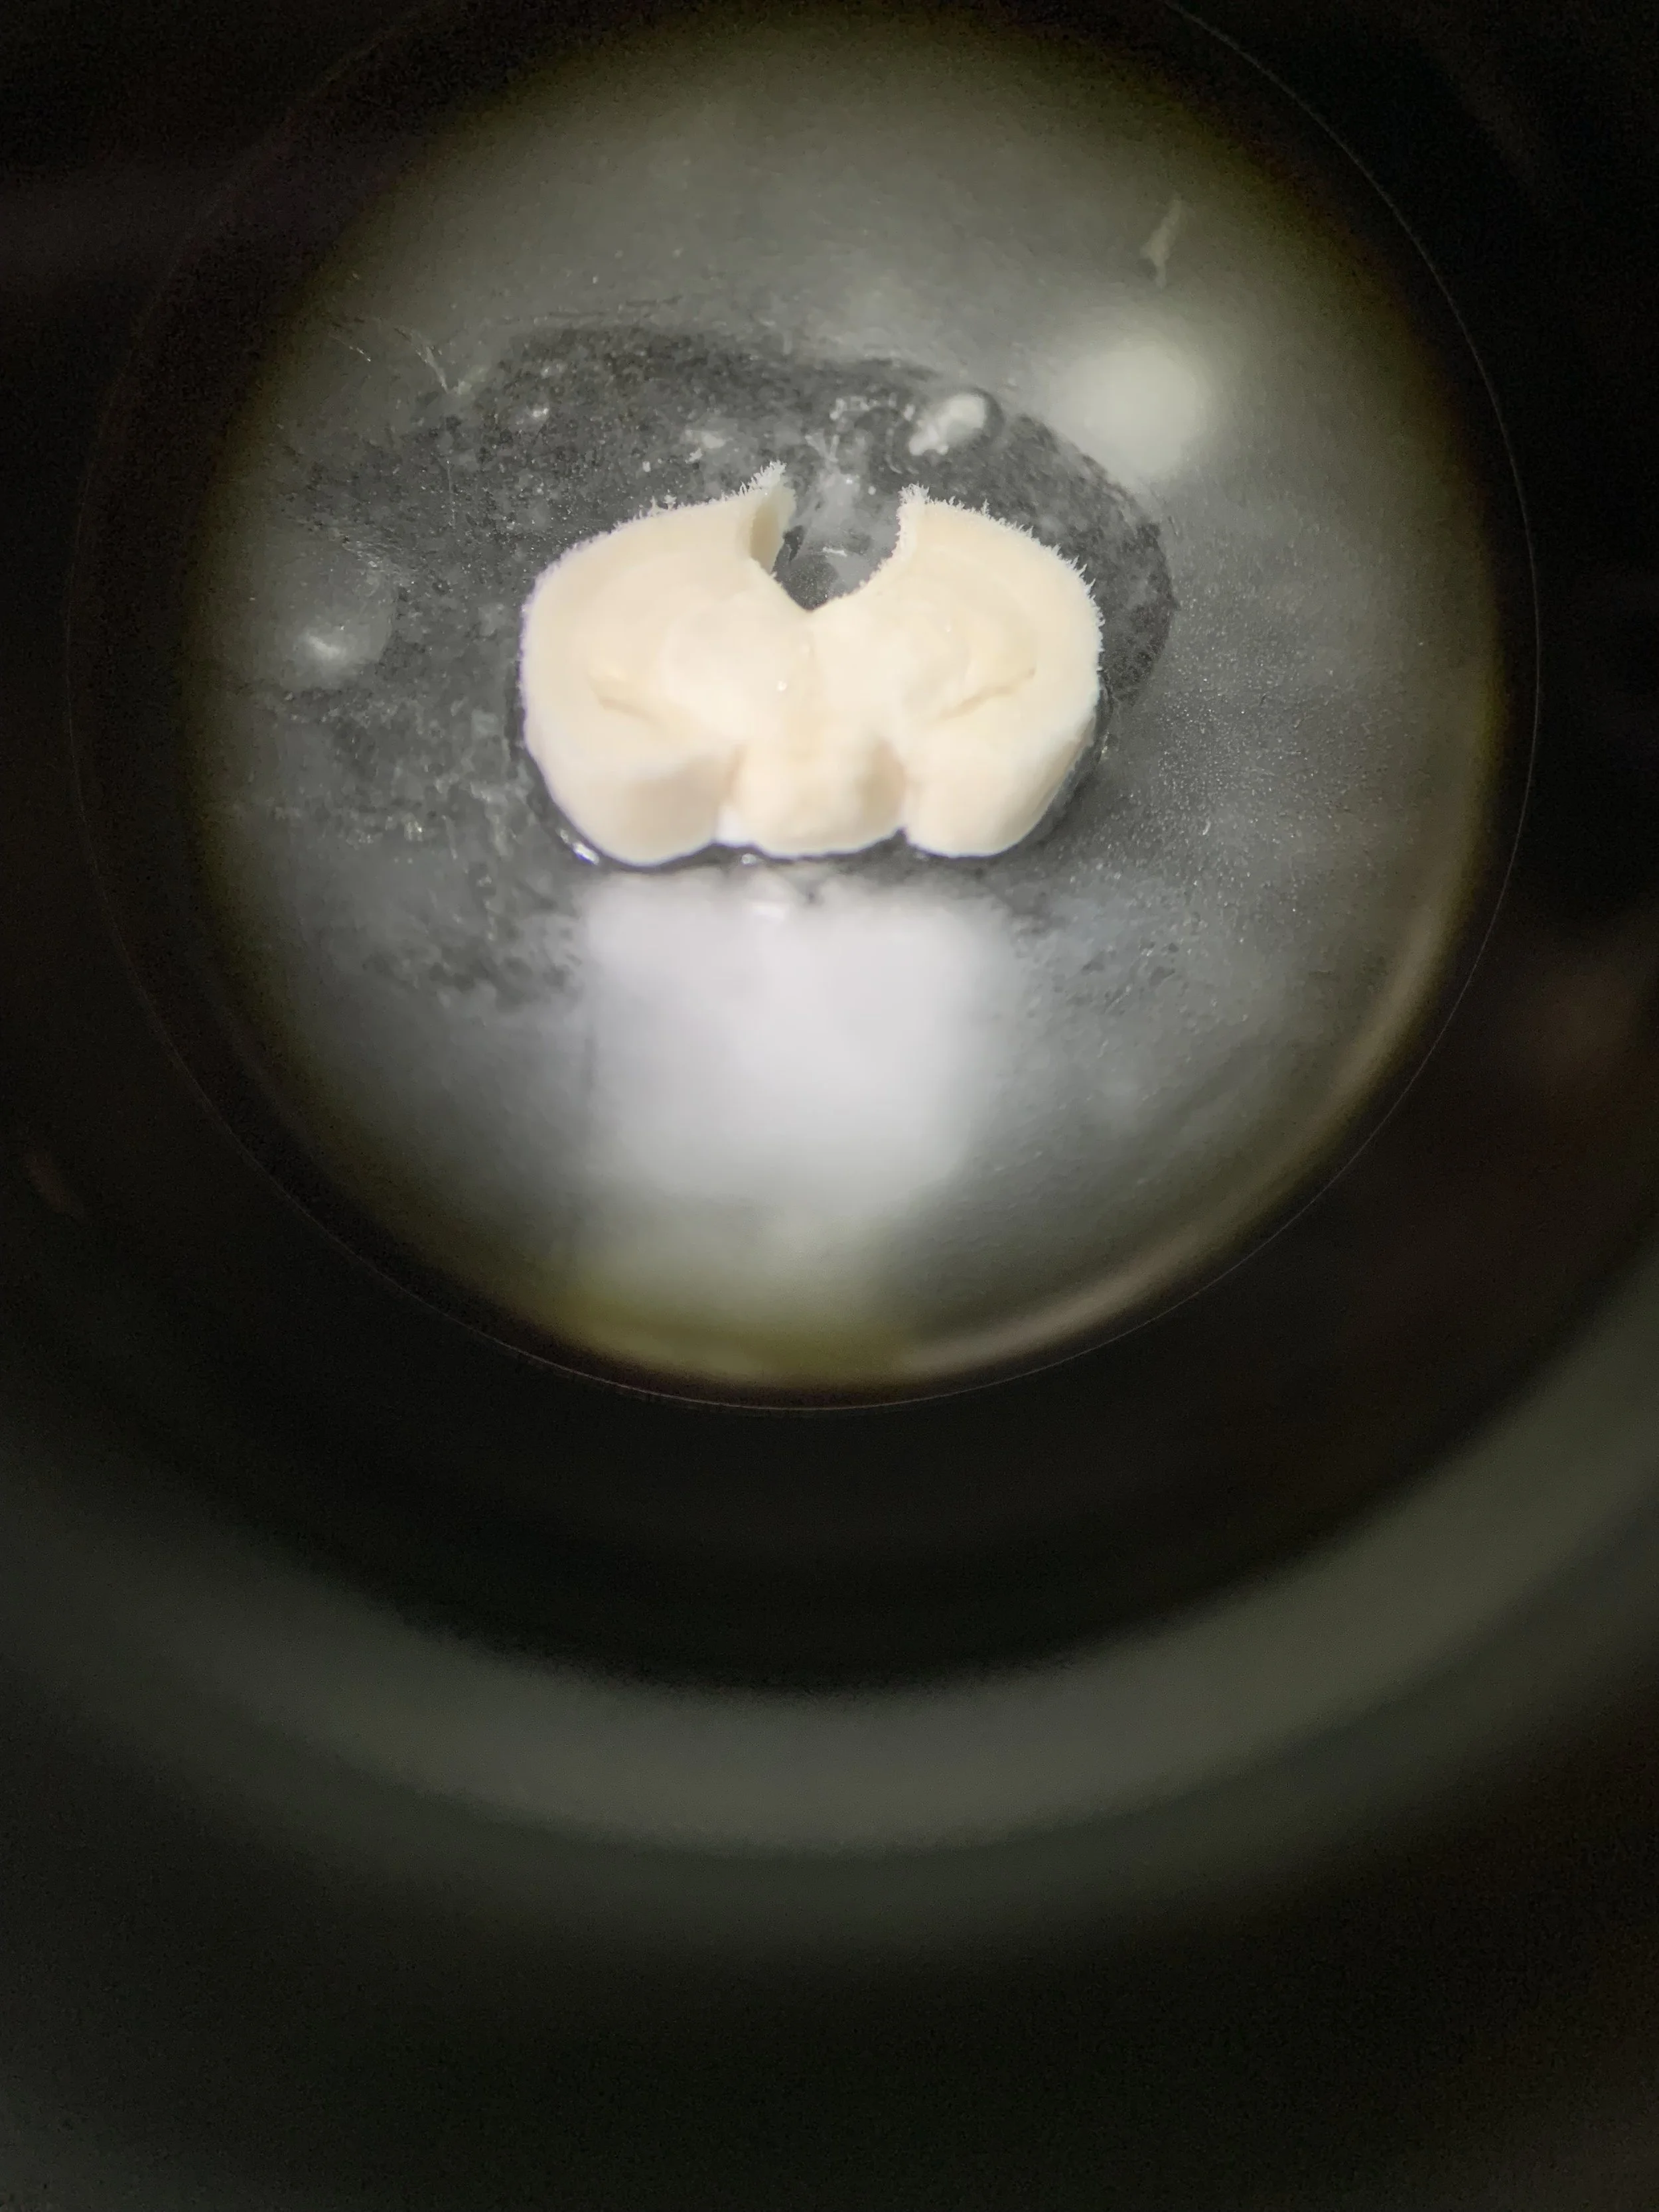

Alzheimer’s Disease is the most common cause of dementia with devastating consequences for patients as well as their families and caregivers. The brain is the most lipid-diverse organ in the body and depends on tight regulation of lipid metabolism and transport to maintain proper neural signaling and cognitive function. We are interested in identifying genes that contribute to dysregulated lipid metabolism that may also affect Alzheimer’s Disease risk and etiology.